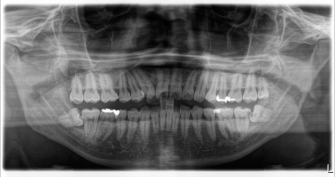

当歯科ではレントゲンをお取りしたり、現状を記録するためにお口の写真を撮らせてもらっています。左のの大きなレントゲンは3割負担の方で1200円、右のお口の写真は150円です。実際にお口の状態を目で見てもらうと一目瞭然。経過を比べると歯肉がどれくらい健康になってきているか、きれいになっているがわかります。そしてそれを記録することに意味があります。

処置も症状が出る前のほうが簡単に済むことが多いです。当歯科では2年に一度はこのレントゲンを撮らせてもらって経過を見ることにしています。症状があればその都度大きいレントゲンではなく、部分的なレントゲンを撮って確認することもあります。小さいレントゲンは150円くらいです。